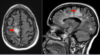

Hyperintensity of bilateral mesial temporal lobes

(recall: video of pt in Giant’s shirt who couldn’t remember Giants won the superbowl) -hallmark = short-term memory loss -psychiatric symptoms (hallucinations, delusions, psychosis, agitation), sleep disturbances, involuntary movements, autonomic dysfunction, seizures